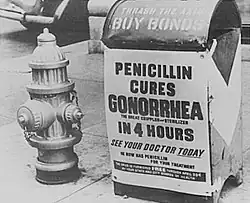

Es ist eine antibiotische Behandlung notwendig. Dies waren ursprünglich ab 1897 das Silberpräparat Protargol, entdeckt von dem deutschen Chemiker Arthur Eichengrün, ab 1935 Sulfonamide von Domagk, und ab 1944 war Penicillin als Behandlung ausreichend.

Ende der 1960er Jahre wurden in Bangkok erste Resistenzen des Erregers Gonococcus gegen Penicilline festgestellt, diese stehen womöglich in Verbindung mit den örtlichen Bordellstraßen.[11] Auf Grund der zunehmenden Resistenzentwicklung der Gonokokken wird die Gabe anderer Antibiotika, beispielsweise Cephalosporine oder Gyrasehemmer (hier besonders Fluorchinolone) empfohlen. Doch auch gegen die Fluorchinolone wird eine zunehmende Resistenz verzeichnet.[12] So empfiehlt das Robert Koch-Institut nur noch Cephalosporine der Gruppe 3 in hoher Dosis, zum Beispiel Ceftriaxon oder Cefixim.[13] Alternativen sind unter anderem Gaben von Cefotaxim oder Spectinomycin. Bei der Ophthalmia neonatorum kommt vor allem Ceftriaxon zum Einsatz.[14] In Japan wurde im Mai 2011 erstmals ein Stamm beschrieben, der gegen alle Cephalosporine Resistenzen entwickelt hat.[15] Inzwischen sind resistente Stämme auch in Australien, Frankreich, Norwegen, Schweden und Kanada[16] aufgetaucht. Die WHO warnte 2012, dass es in absehbarer Zeit für Millionen Infizierte keine Heilung mehr geben könne.[17]

Seit 2019 gibt es eine aktualisierte S2K-Leitlinie zur „Diagnostik und Therapie der Gonorrhoe“. Demnach wird für die Behandlung der unkomplizierten Gonorrhö eine Kombination der Antibiotika Ceftriaxon und Azithromycin empfohlen.[18][19]

Bei einer komplizierten Gonorrhoe werden die gleichen Antibiotika über einen längeren Zeitraum (sieben Tage bis einen Monat) angewendet. Neugeborenen-Infektionen können durch Vorsorgeuntersuchungen bei Schwangeren heute weitestgehend vermieden werden.